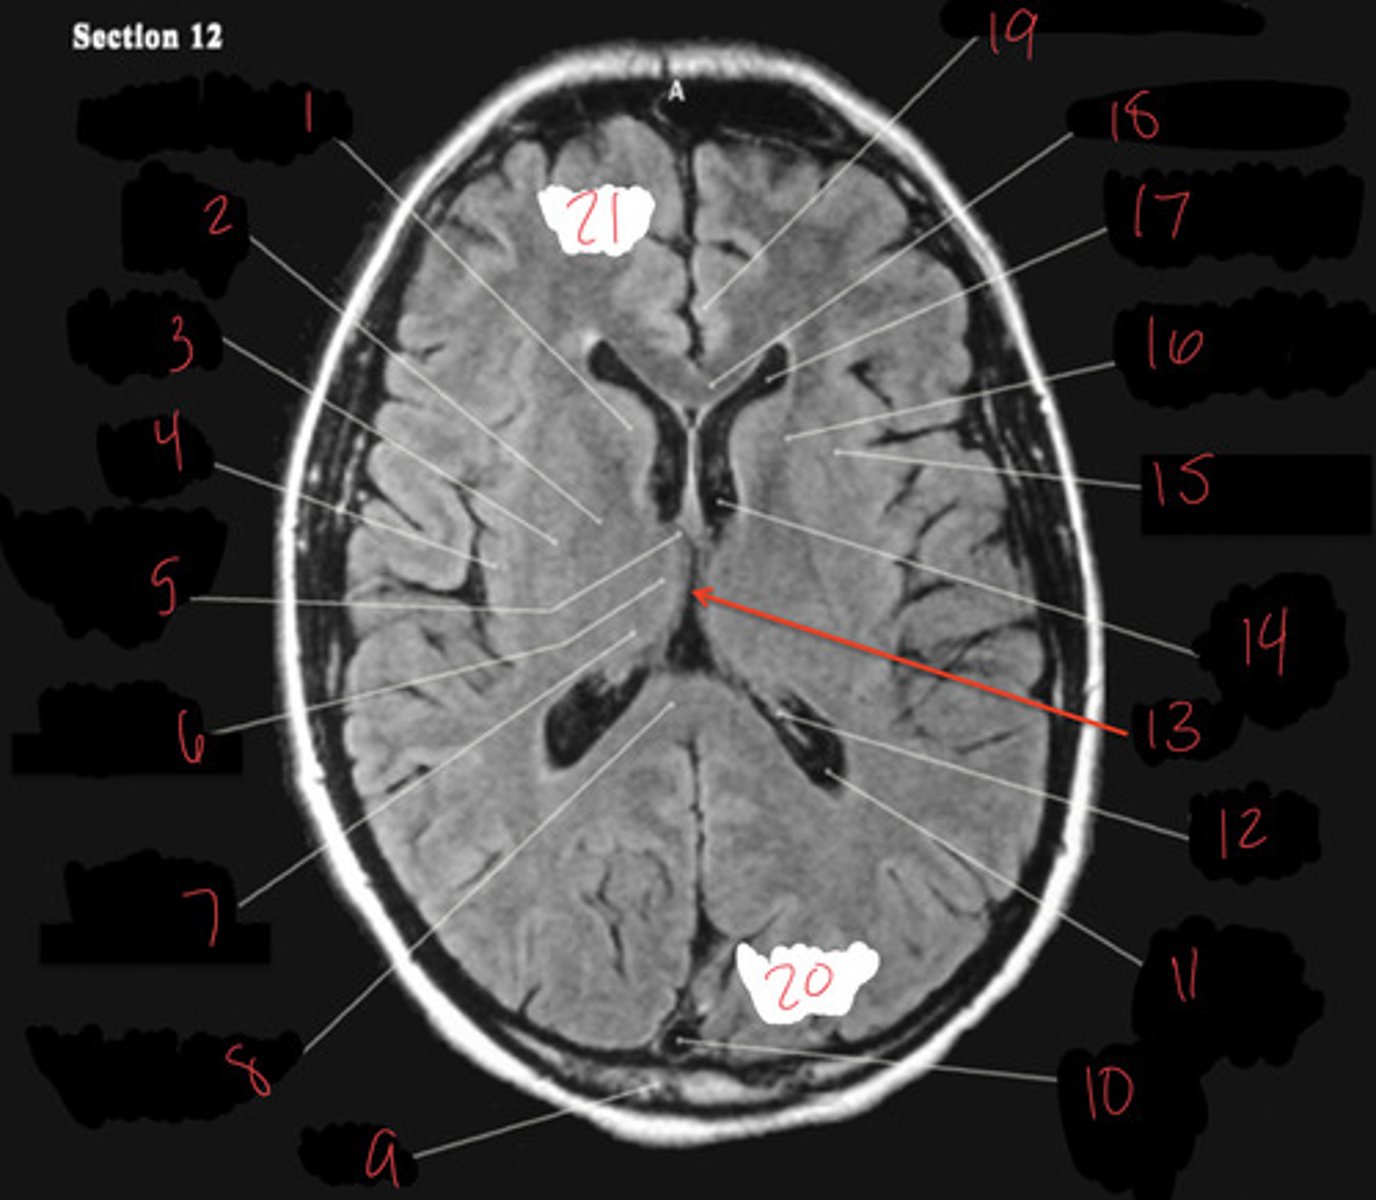

thalamus

heart shaped, deep in the brain, hugs the third ventricle. Referred to as the relay center.

Basal Ganglia

structures in the forebrain that help to control movement. Composed of three main parts: the caudate nucleus, the putamen, and the globus pallidus

Caudate nucleus

One of the major nuclei that make up the basal ganglia. Head: Anterior to the thalamus, forming the lateral wall of the lateral ventricle.

Body: Extends posteriorly and laterally from the head, parallel to the thalamus.

Tail: Curves inferiorly and medially, lying above the temporal horn of the lateral ventricle.

Putamen

involved in motor control and learning

Globus Pallidus

more medial than putamen, appears with the third ventricle.

internal capsule

White matter pathway is lateral to the caudate nucleus, between the caudate and the putamen (and globus pallidus). It carries primarily motor fibers, including corticospinal tract fibers.

third ventricle

thin midline space that separates the left and right thalami.

interthalamic adhesion

Connects the two thalami and passes through the third ventricle.